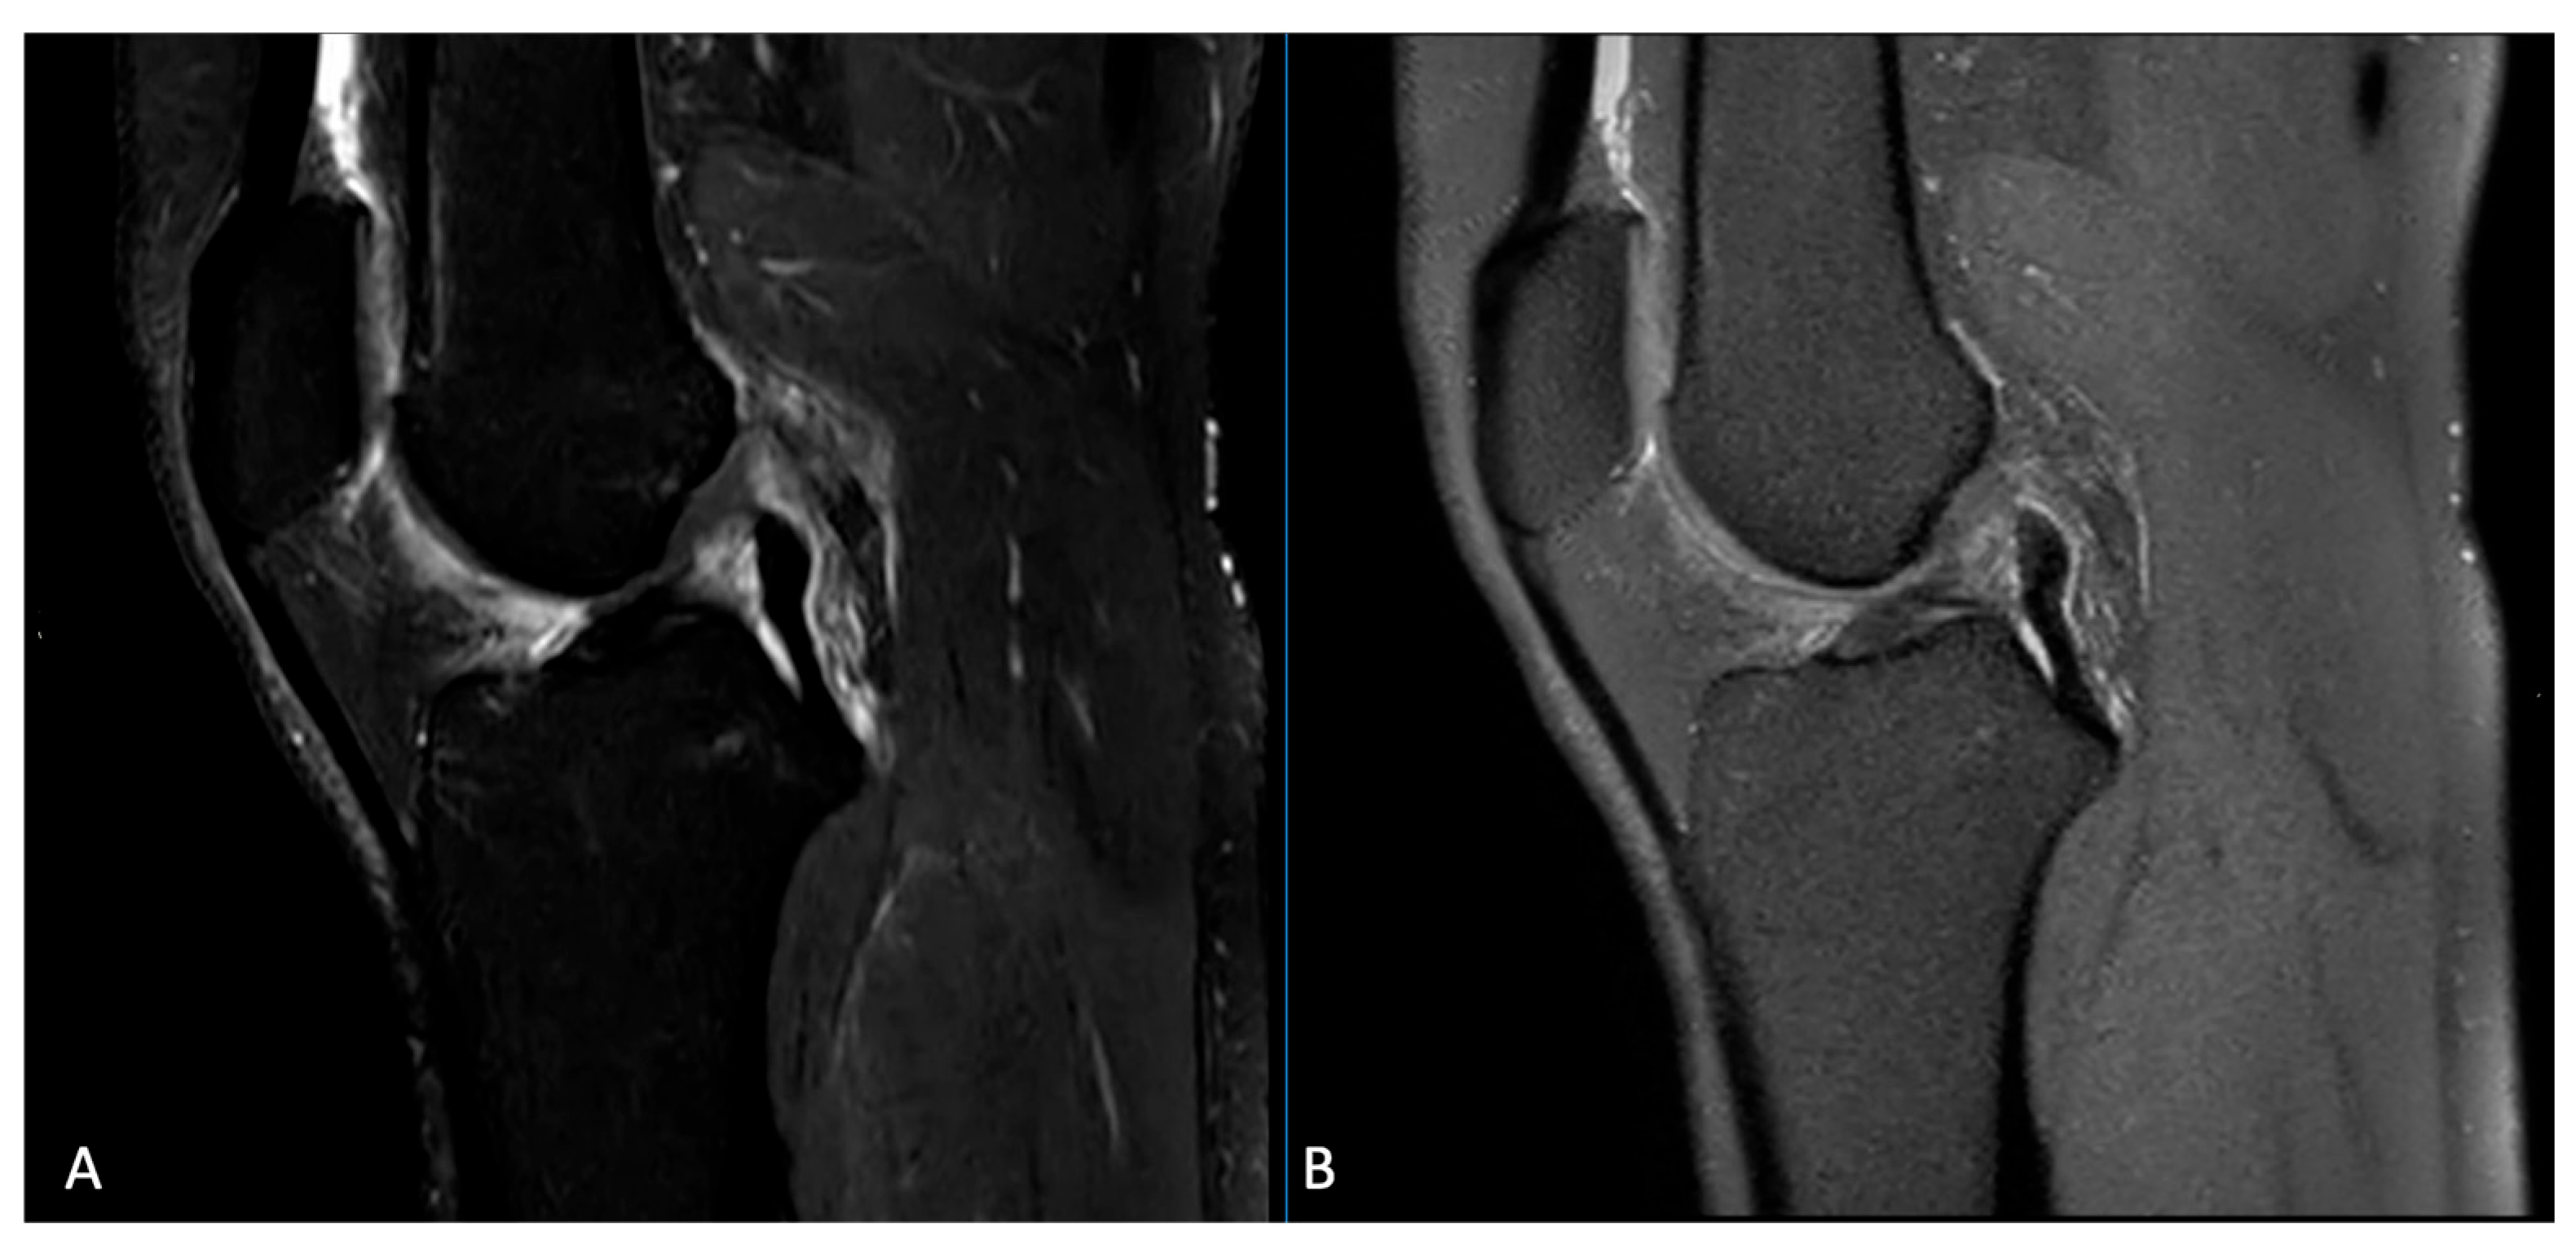

3.3. Pathological Entities

4. Discussion